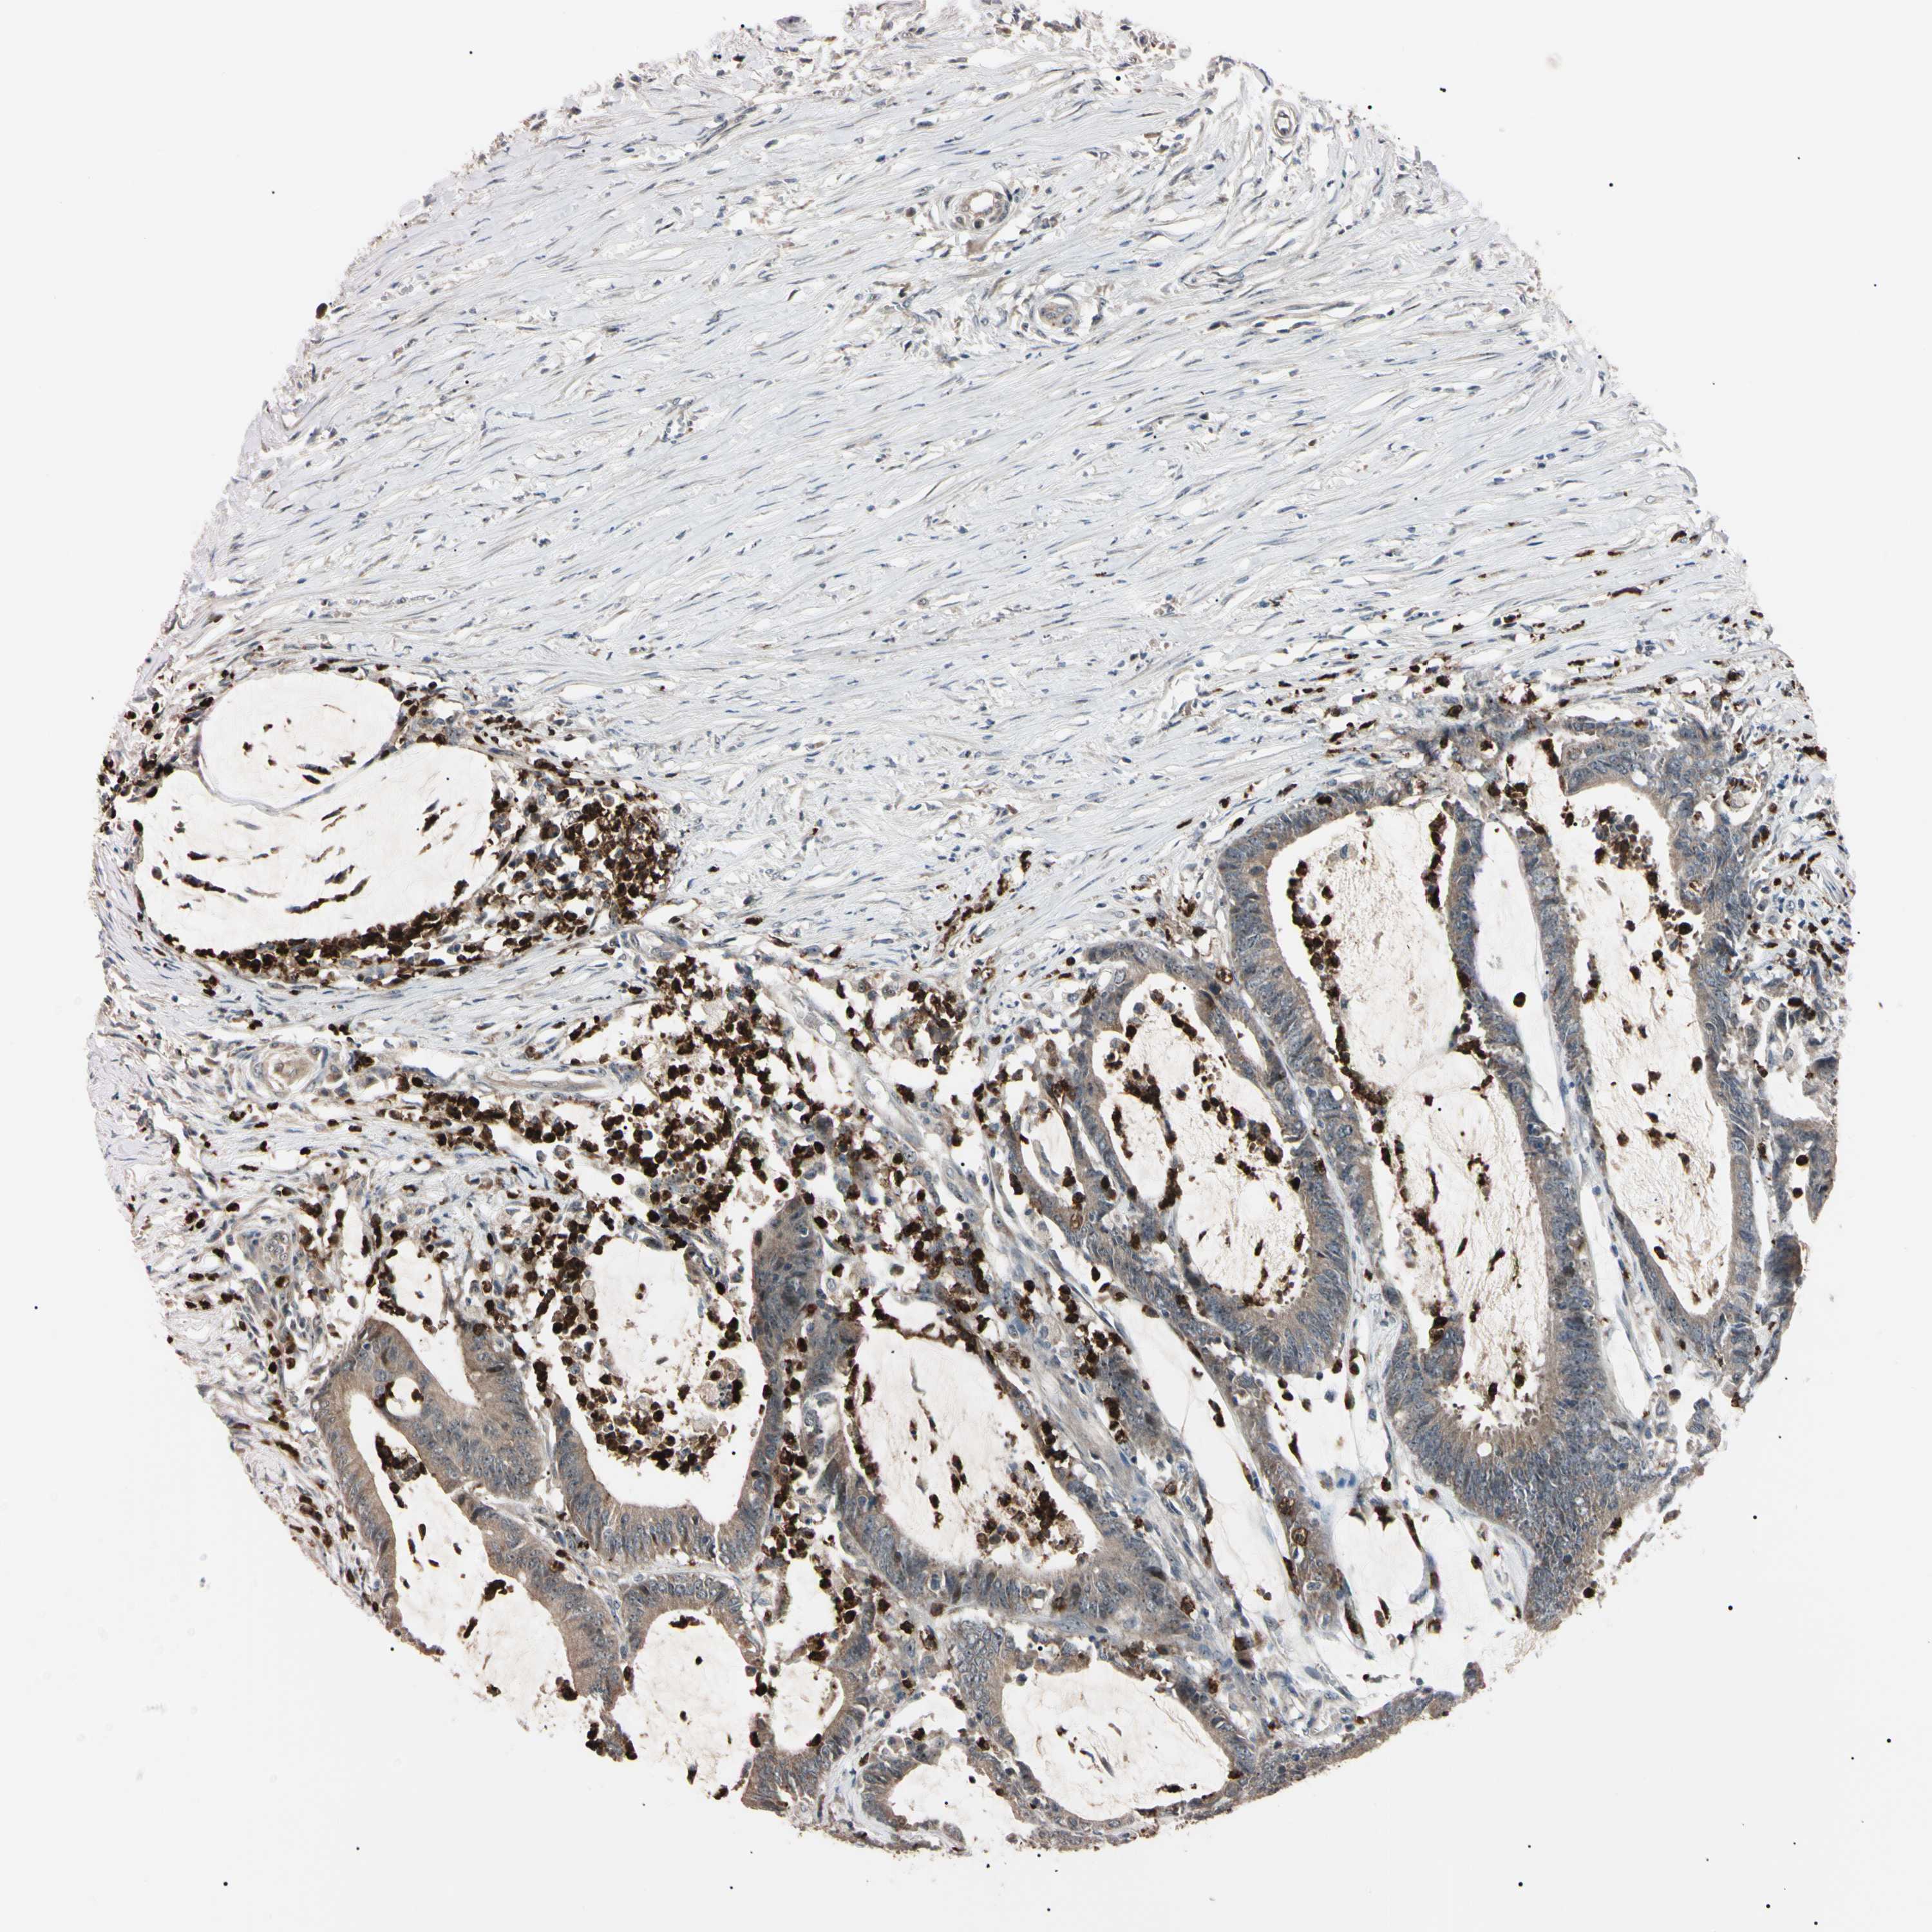

CANCER COLORECTAL CANCER Show tissue menu

Colorectal cancer

Human cancer

Colon adenocarcinoma